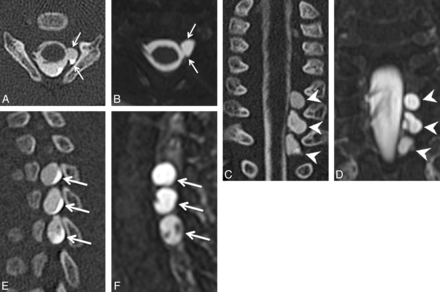

Axial (A), coronal (C), and left parasagittal (E) images from a CT myelogram and corresponding axial (B), coronal (D), and left parasagittal (F) images from an MR myelogram (B, D, and F) on the same patient demonstrating 3 consecutive left-sided pseudomeningoceles with absent rootlets at C7–T1 (arrows in A and B, arrowheads in C and D, arrows in E and F). Note the internal septa within the middle and lower pseudomeningoceles that can simulate intact rootlets on a single image.